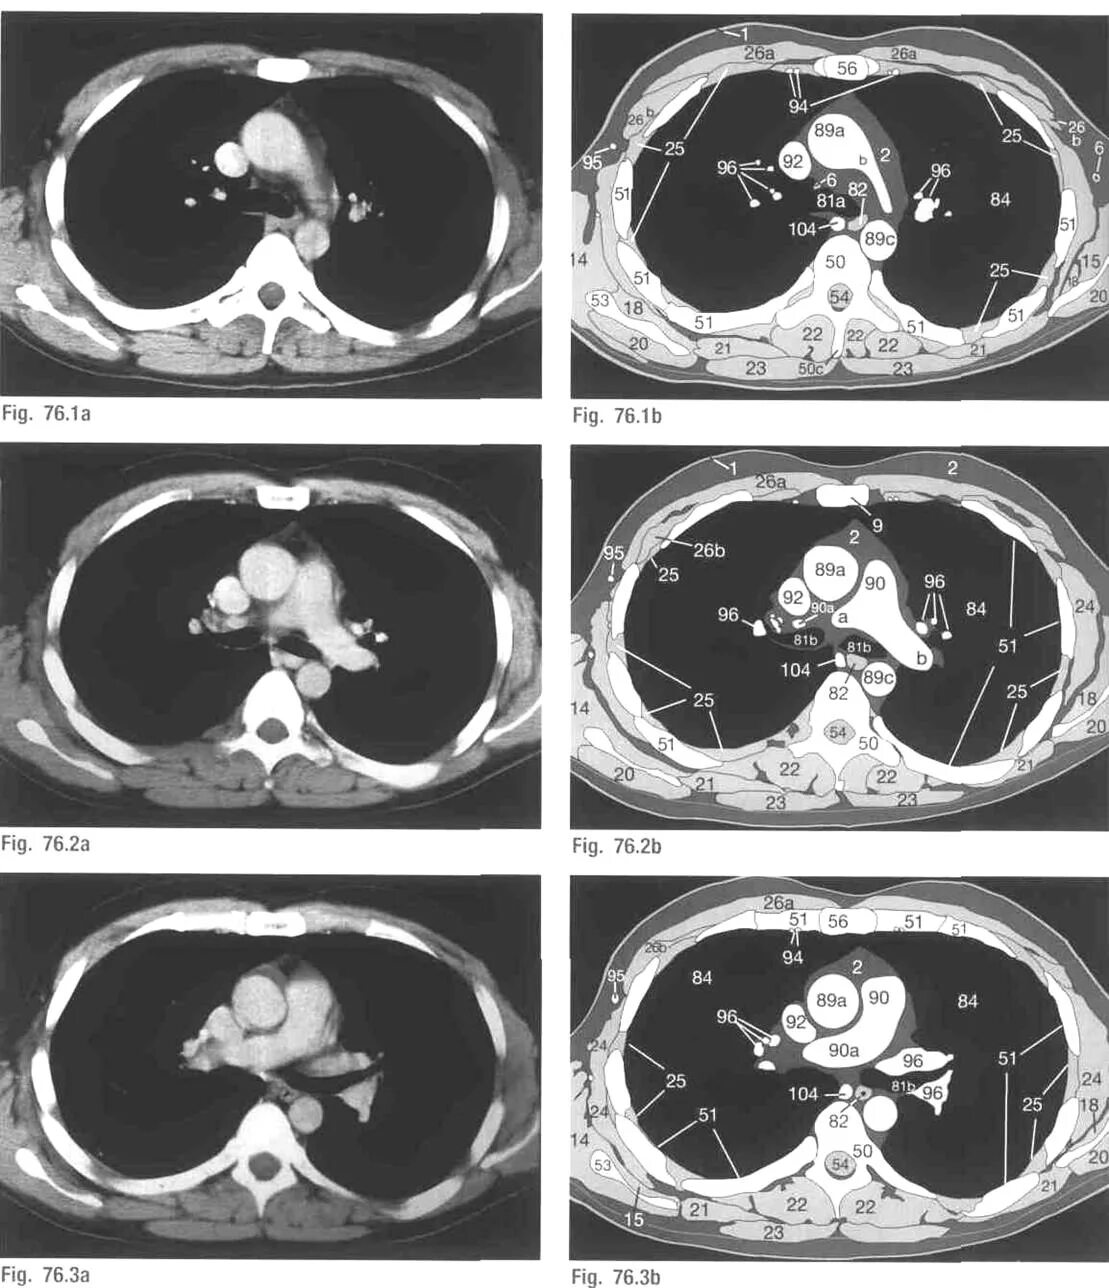

Легочный ствол на кт